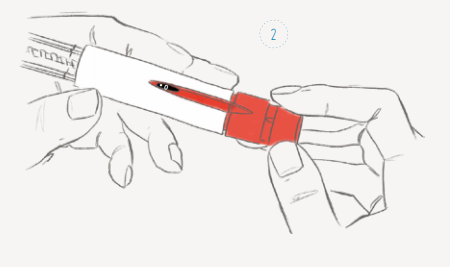

Stimulatie vindt vrijwel altijd plaats door toediening van de Gonal-F ® via een dagelijkse onderhuidse injectie die u zelf injecteert. Indien u geen ervaring met injecteren heeft, is er een prikinstructie door de verpleegkundige mogelijk. De dosering van de Gonal-F ® is afhankelijk van een aantal factoren waaronder het aantal beschikbare eiblaasjes, uw leeftijd en de reactie op eventuele eerdere hormoonbehandelingen.

Figuur 5. Het injecteren van de Gonal-F (afbeelding van Merckgroup).